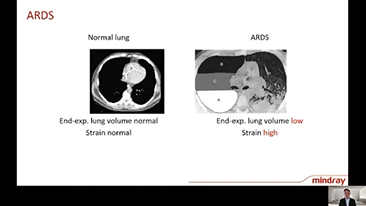

A escolha das configura??es corretas do respirador para o tratamento de pacientes com doen?as do trato respiratĂłrio Ă© uma quest?o muito importante. Como a tarefa de especificar os par?metros do equipamento de ventila??o Ă© inteiramente realizada por um mĂ©dico, o conhecimento e a experiĂȘncia do mĂ©dico na sele??o desses par?metros tem um efeito direto na precis?o de suas decis?es. O paradigma do atendimento de apoio aos pacientes mudou significativamente ao longo dos Ășltimos 20 anos. Atualmente, vĂĄrios modos de ventila??o e ferramentas de apoio Ă decis?o foram desenvolvidos em torno das necessidades clĂnicas para ajudar os profissionais clĂnicos a melhorar a eficiĂȘncia e eliminar os erros nas decis?es clĂnicas.

Integrando oxigenoterapia de alto fluxo, ventila??o n?o invasiva e ventila??o invasiva, os respiradores 3 em 1 da sĂ©rie SV reĂșnem desempenho estĂĄvel, fun??es versĂĄteis e facilidade de uso. Os recursos excepcionais de prote??o pulmonar e as vĂĄrias ferramentas de apoio Ă tomada de decis?es dos respiradores s?o projetados para diminuir o risco de infec??es cruzadas e facilitar a rotina diĂĄria dos profissionais clĂnicos.